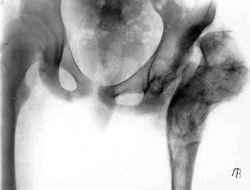

Results of treatment.Results of treatment.

Results of treatment.

Results of treatment (Patient).Results of treatment (Patient).Results of treatment (Patient).

Results of treatment (Patient).